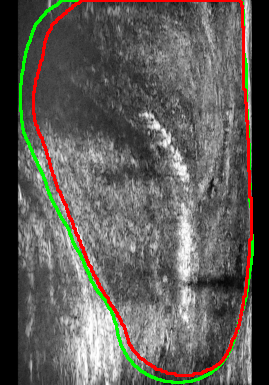

This study utilizes the Micro-ultrasound Prostate Capsule Segmentation dataset[16], which consists of micro-ultrasound images from 75 patients specifically curated for prostate segmentation tasks. The dataset is divided into a training set comprising 2,750 images from 55 patients and a testing set containing 600 images from 20 patients. Each patient’s dataset includes approximately 200–300 micro-ultrasound images acquired in a pseudo sagittal plane. The images were normalized to an intensity range of [0, 1] and resized to 224x224 pixels to maintain a consistent scale and size for practical neural network training. Furthermore, various data augmentation techniques, such as random rotations, flips, and intensity variations, were applied to the training images. The dataset was annotated by experts and non-experts, with all annotations reviewed and refined to ensure high-quality ground truth. Annotation discrepancies were used to identify hard and easy regions incorporated into the AG-BCE loss function. Figure 2 illustrates the sample images of the dataset.

Figure 4 presents the performance evaluation of three loss functions—Adaptive Focal Loss, AG-BCE Loss, and PyTorch Focal Loss—on three test images. Each row in the figure corresponds to the segmentation results of one loss function, while the columns represent the respective test images. A legend at the top provides the color coding for the ground truth and the outputs of the three loss functions, allowing for a direct visual comparison of their performance.

The visual analysis of segmentation results, illustrated in Figure 5, demonstrates that Adaptive Focal Loss consistently achieves more accurate segmentation, particularly in regions with low contrast, high noise, or complex anatomical variations, closely aligning with the ground truth.

Test Image 04: The Adaptive Focal Loss function excelled in capturing the prostate boundary, especially in the lower-left region obscured by speckle noise. By comparison, AG-BCE and PyTorch Focal Loss exhibited significant deviations, notably under-segmenting the prostate and failing to depict the boundary accurately.

Test Image 11: The Adaptive Focal Loss function demonstrated superior performance in the upper-right region, where the prostate boundary was subtly defined against surrounding tissue. AG-BCE failed to capture finer details, producing a less smooth boundary and shifting it inward, while PyTorch Focal Loss over-segmented, extending beyond the prostate.

Test Image 14: Despite complex artifacts in the lower region, Adaptive Focal Loss maintained a boundary closely resembling the ground truth. AG-BCE exhibited minor mismatches, particularly in the lower-right corner, while PyTorch Focal Loss underperformed, displaying over-segmentation and boundary deviations.